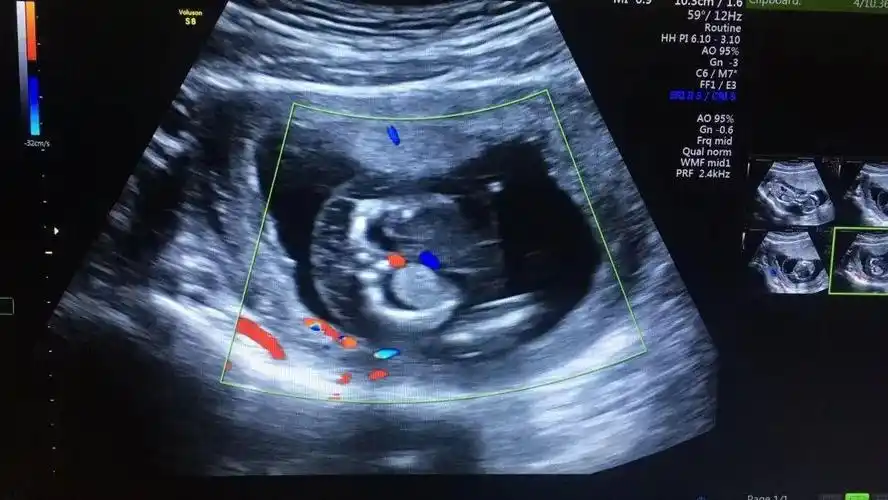

粗心孕妈14周才做首次产检仁爱医院及时筛查出胎儿严重畸形